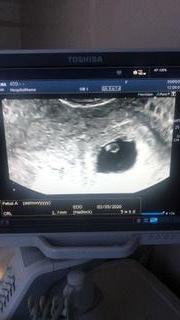

Вот такие мы были в 4.3 Эмбриональные недели. А первое фото 3.1 так что все очень быстро растёт и думаю через недельку все точно будет видео и понятно! Растите 🙏🏽🙏🏽